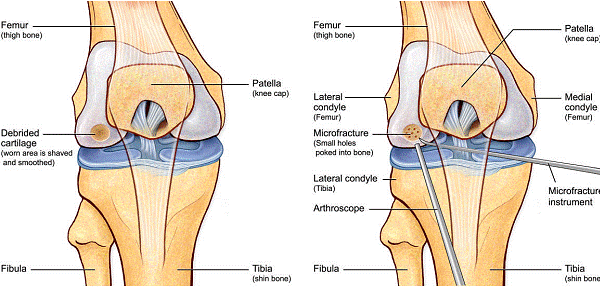

Chirurgul trebuie sa fie foarte atent atunci cand examineaza posteriorul condililor femurali. Daca se semnaleaza orice vatamare/rana/deteriorare pe suprafetele articulare, trebuie sa se cerceteze atent calitatea cartilajului. Orice flapsuri instabile sunt inlaturate prin folosirea unui aparat de ras electric artroscopic sau curette. Apoi, un curette este folosit pentru a debrida stratul de cartilagiu calcifiat de la baza in toata grosimea defectului. Acest pas se bazeaza pe activitatea lui Frisbi, care a demonstrat vindecarea suprafetei articulare superioare la un cal, cand stratul cartilagiului calcifiat este indepartat. Cand indepartam stratul cartilajului calcifiat, in general nu se foloseste un aparat de ras. Cu un aparat de ras este dificil de controlat cantitatea de os eliminat, si este posibil ca osul subcondral sa fie afectat.

Dupa indepartarea cu succes a stratului de cartilaj calcifiat, o andrea este folosita pentru a face mai multe gauri mici (mirofracturi) in osul expus al defectului condral aflate la distanta de 1-2 mm. Trebuie lasata o punte de oase potrivita intre gauri. Tehnica de microfracturi are numeroase avantaje fata de foraj. Mai intai de toate, creaza o leziune termala mai mica. Mai mult, cu microfracturi chirurgul este capabil sa intre in zonele dificile ale suprafetei articulare cu un control mai bun asupra adancimii de patrundere. La finalizarea microfracturii, o suprafata aspra este generata pentru aderenta cheagului de sange care contine celule mezenchimale nediferentiate de la osul subcondral. Trebuie avut grija ca cele mai marginase parti ale leziuni sa fie patrunse de andrea pentru a ajuta la vindecarea tesutului reparator la imprejmuirea suprafetei articulare. Odata ce microfractura este finalizata, pompa artroscopica este oprita pentru a se asigura ca sangerarea maduvei curge din gaurile mici umpland defectul.[54]

Fig.23. Diagrama microfracturi: a. Leziunea; b. Rezultatul interventiei.

Andrelele de microfracturare cu unghi reglat actioneaza moderat astfel incat gaurile verticale pot fi facute fara daune termice. Se fac gauri chiar de la marginea defectului.

Fig.25.a. Debridarea. Fig.25.b. Microfracturare.